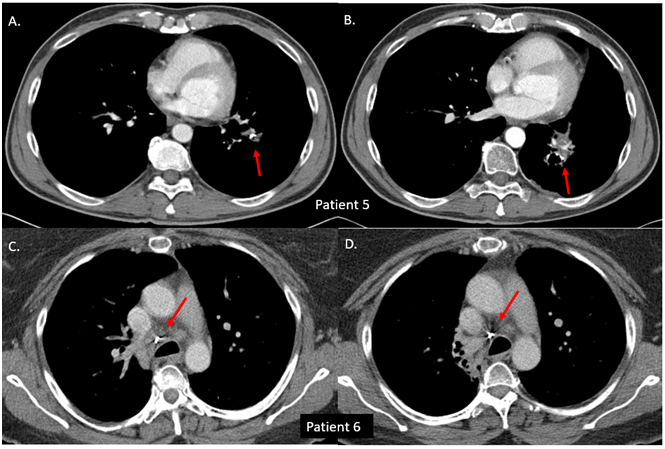

Figure 2 Coils with stable position during follow-up. Patient 5-left intrapulmonary fiducial-A. Initial placement and B. 6.5-year follow-up. Note the posteromedial displacement of the coil due to fibrotic changes of the irradiated lung tissue. Patient 6-right para-tracheal fiducial-C. Initial placement and D. 6-year follow-up. All three fiducial markers in this patient were visualized at 6 years in the same location as the original placement.